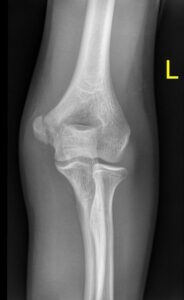

Grafi kararı alınan hastada Antero-Posterior(AP) ve Lateral grafi standart olarak ilk yapılan görüntülemelerdir.

AP grafi çekilirken dirsek tam ekstansiyonda ve önkol supinasyonda olmalı.